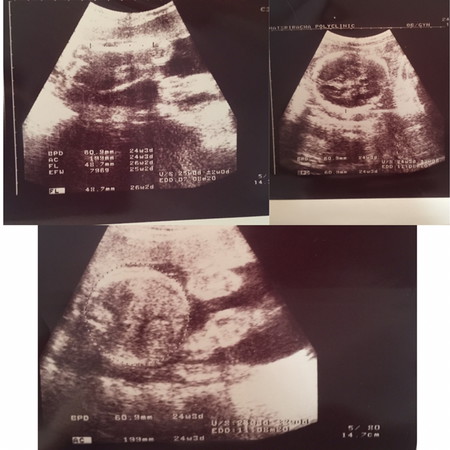

แม่ๆคะ ตรงไหนคือเบบี๋คะ และเพศอะไร บ้านนี้ดูไม่ออกเลยค่ะว่าเบบี๋คือส่วนตรงไหน รูปซาวไม่ชัดเลยค่ะ

คิดว่ารูปแรกเป็นช่วงก้นน้อง(น่าจะ ญ นะคะ) รูป 2-3 เส้นรอบหัวกับท้องน้องค่ะ